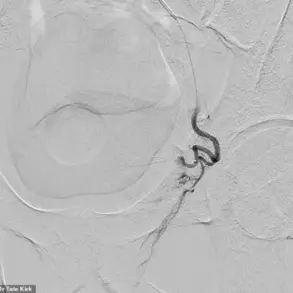

Graphical data from the research underscores the disparity between groups with and without OSA.

Over a six-year follow-up period, the group with OSA (represented in blue) experienced a notably higher number of new Parkinson’s diagnoses compared to the group without OSA (depicted in orange).

This visual representation reinforces the urgency of identifying and treating sleep apnea as a potential preventive measure for Parkinson’s.